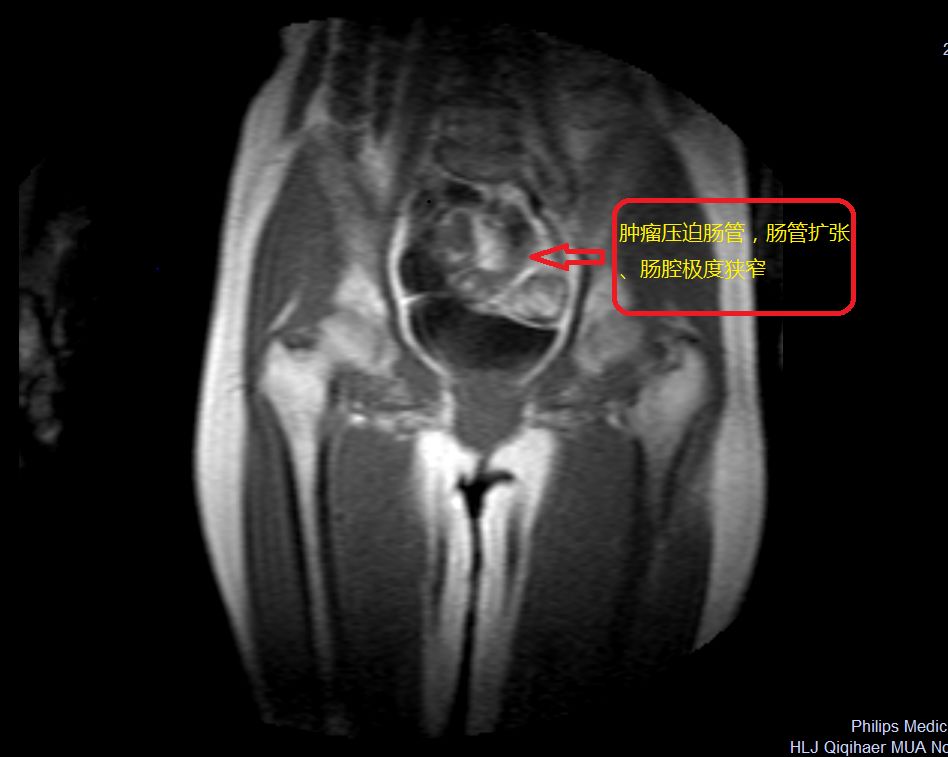

患者许某,54岁,因发现直肠癌7日余来我院就诊,入院后完善相关检查,MRI检查示:S1-2椎体水平直肠壁占位,考虑直肠癌。

术前影像资料